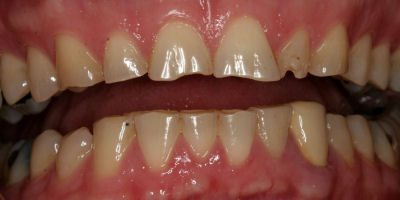

Opening Bite